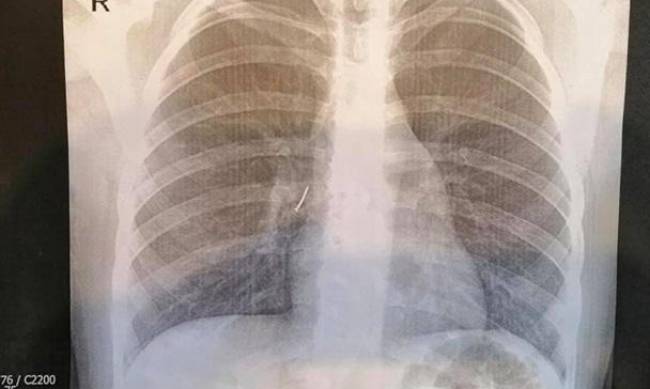

Маленькую пациентку скорой из Ходоровской городской больницы госпитализировали во Львов. Ребенку сделали рентген-снимок и слова пациентки об инородном теле в бронхах подтвердились - на снимке был четко виден гвоздь.

"Из правого промежуточного бронха ребенка мы достали канцелярский гвоздь с пластмассовой частью и острием. Это было непросто, ведь пластмассовая часть гвоздя полностью перекрыла бронх так, что нижняя доля правого легкого почти не функционировала", - рассказал врач Александр Колодий, который оперировал ребенка.